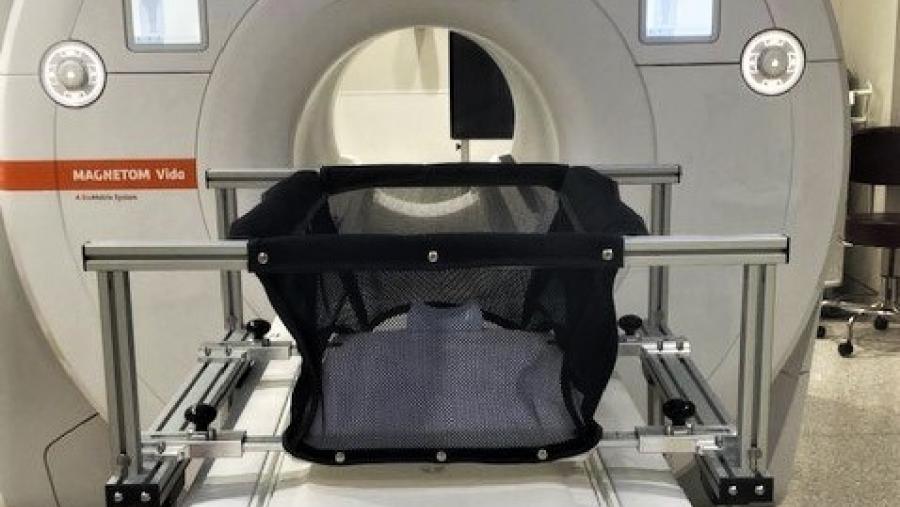

HEAL-funded researchers are investigating the role of sleep deficiency in opioid use disorder and relapse risk

Published: October 28, 2021

Topics:

Sleep Dysfunction